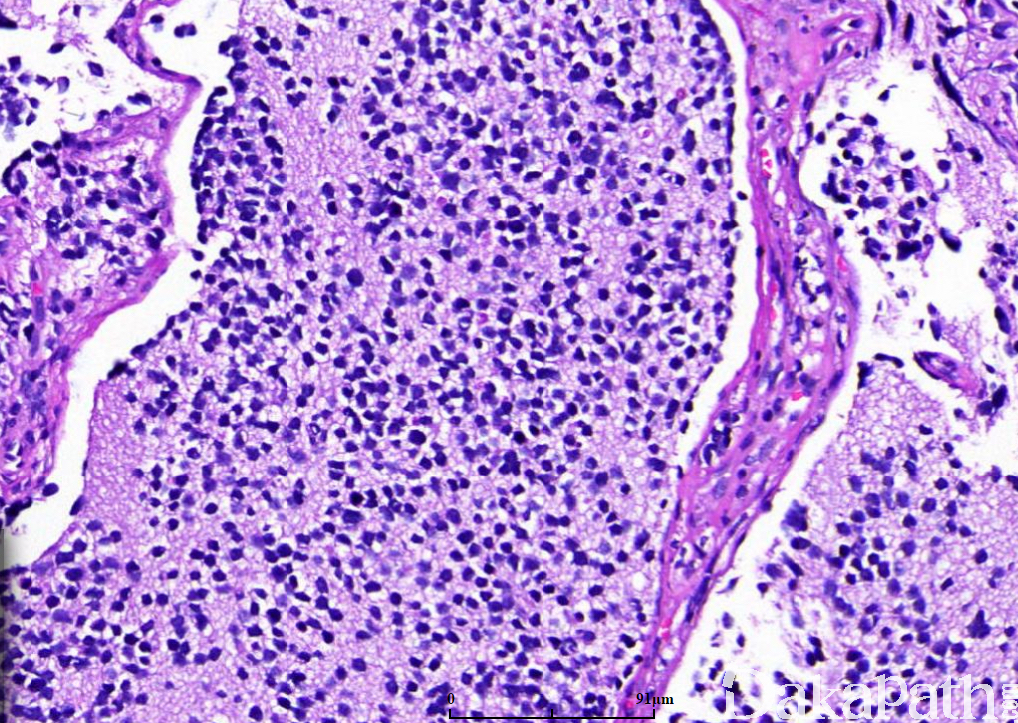

瘤细胞小而一致,胞浆稀少,染色质细腻,核仁不明显,核分裂象较活跃;神经节细胞分化< 5%,神经节细胞分化定义为瘤细胞的胞体和胞核同时增大,细胞的直径 2 倍或以上于核的直径(诊断神经节细胞分化所必须),可见丰富的双嗜性胞浆,核偏位伴有空泡状染色质以及明显的核仁;部分细胞表现为未分化神经母细胞瘤和成熟的神经节细胞之间的过渡状态,表现为瘤细胞核轻度增大伴有开放的染色质和明显的核仁;

瘤细胞核染色质呈粉尘状或点彩状,神经节细胞分化< 5%;